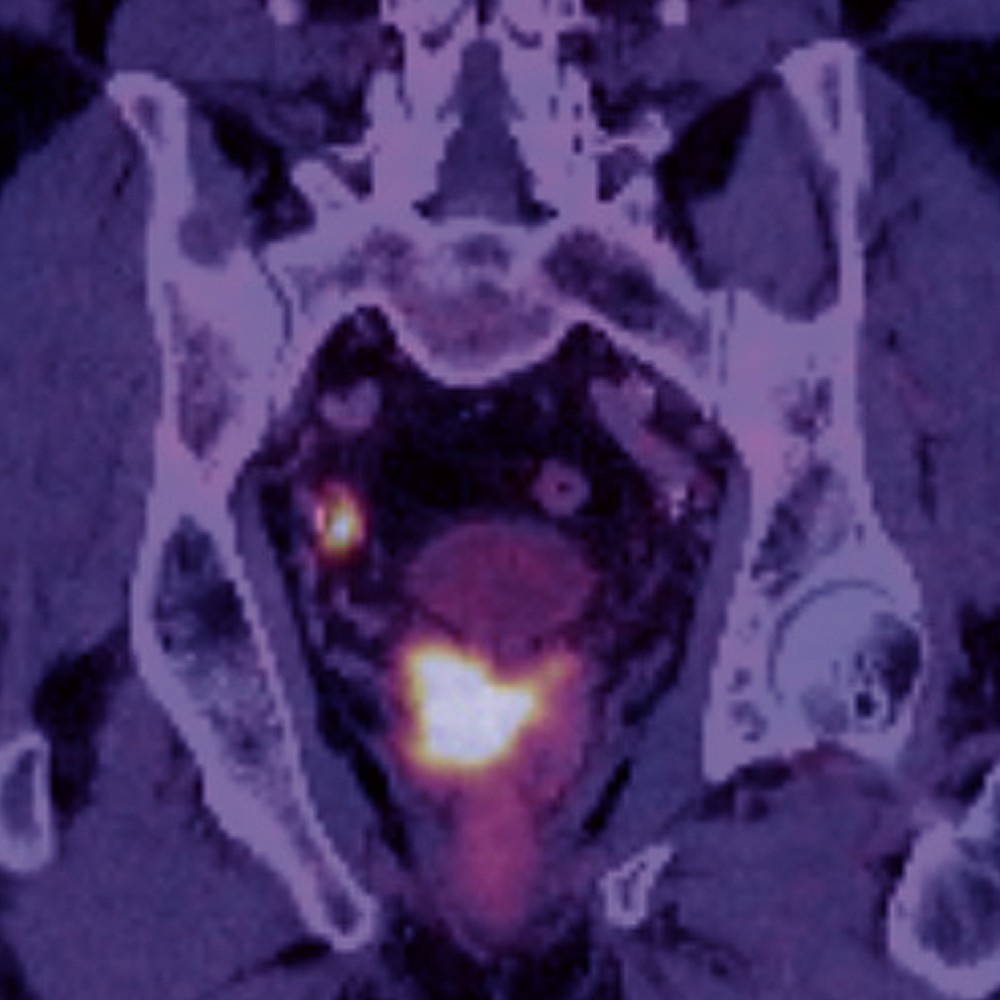

Willkommen zum 16. Petersberger Symposium – dem zentralen Treffpunkt für Expertinnen und Experten der klinischen Radiologie. Unter dem Motto „Radiologie meets Urologie“ widmen wir uns 2026 der Zukunft des Prostata-Screenings: von technischer Innovation über künstliche Intelligenz bis hin zu neuen diagnostischen und therapeutischen Standards.

Zukunft des Prostata-Screenings

• Innovative Bildgebung und Screeningstrategien

• Fortschritte in der MRT-basierten Diagnostik